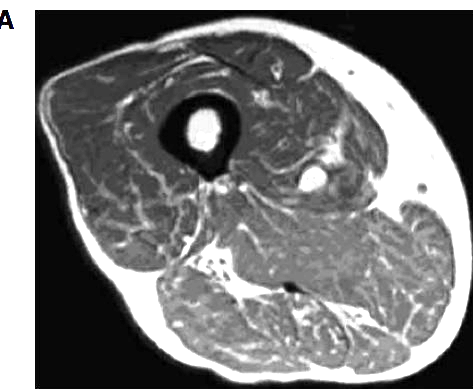

Figure 1

Cross-sectional computed tomography at the level of the middle thigh showing fatty degeneration and atrophy of skeletal muscles in a vitamin D-deficient patient.